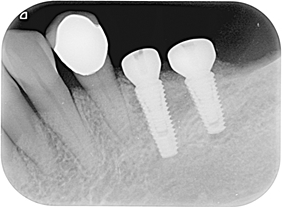

分別植牙後X光片